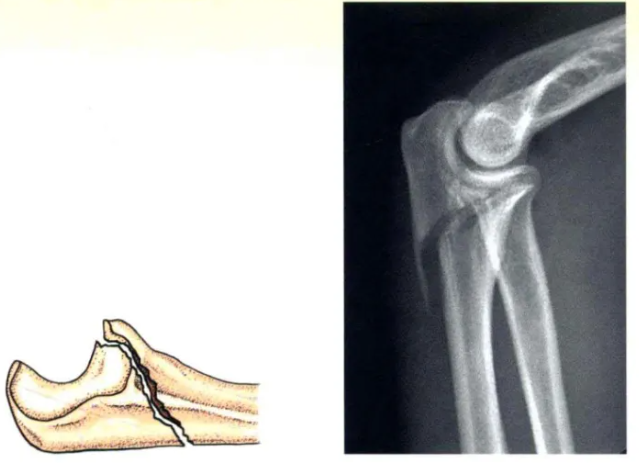

C型:斜(xie)形骨折(zhe)

C型:由(you)拉力(li)螺釘產生骨(gu)折間加(jia)壓(ya),并(bing)由(you)接骨(gu)板或張力(li)帶提供(gong)保(bao)護(“中和”)